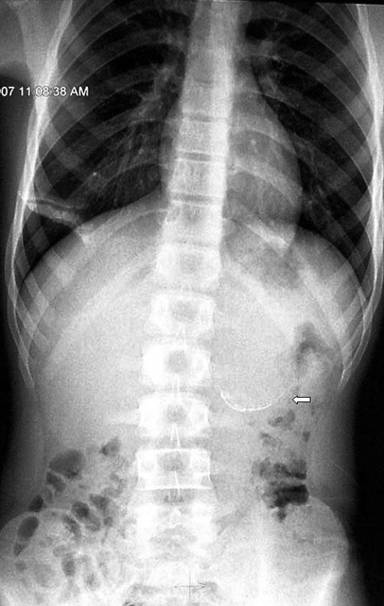

Plain X-ray of the abdomen revealed classical curvilinear calcification in only one patient with a hydatid cyst in the pancreatic body (Figure 1). Ultrasonographic examination which recorded the site, size and extent of the lesions, documented the cystic lesions as anechoic rounded structures in all cases. An abdominal CT scan documented the cysts as spherical hypodense space-occupying lesions. All the lesions were solitary, measuring 26-50 mm in diameter (mean 36.7 mm). Five lesions were cystic with thin walls and one lesion appeared as a multiseptated cyst. Magnetic resonance imaging for defining the lesion and its relationship with the pancreatic duct was performed in three patients (two lesions in the head and one in the body of the pancreas). Two lesions were located in the head (Figure 2, 3, 4, 5), two in the body (Figures 6 and 7) and two in the tail region of the pancreas (Figure 8). In two cases, a preoperative diagnosis was possible due to the presence of classical features which also included a concomitant hydatid cyst in the liver in one patient. All patients underwent surgical exploration; intraoperative cyst puncture for aspiration cytology was successful in three cases (two cases with cysts in the head and one case with a cyst in the body of the pancreas); the results of cytological examination were positive in all cases. A fragmented laminated membrane was observed in two patients, scoliosis in three and hooklets in one patient (Figure 9). The laminated membrane was seen as a foliated, acellular, pale, eosinophilic structure which stained strongly positive with periodic acid Schiff staining and negative with alcyan blue staining. The hooklets had a characteristic shape presenting as a blade, a guard and a root. They were not stained with Papanicolaou stains and their appearance was enhanced by turning down the microscope condenser. There were no complications after diagnostic aspiration. In all three cases, the aspirated fluid was colorless and contained a mean sodium level of 128 mEq/L (range: 128-130 mEq/L), chloride level of 69 mEq/L (range: 65-70 mEq/L) and potassium level of 5.8 mEq/L (range: 5.4-6.3 mEq/L). Cysts in the distal pancreas observed in the two patients were treated by a distal pancreatectomy with splenectomy. Cysts in the body were treated by a pericystectomy in one patient (Figure 10) and a central pancreatectomy in another patient. Cysts in the head region in two patients were treated with evacuation, partial cystectomy and tube drainage of the cavity after protecting the surgical area with a scolicidal solution (Figure 11). Both patients underwent T-tube drainage of the common bile duct; there was rapid regression of the jaundice in these patients. The T-tube cholangiogram confirmed the free flow of bile into the duodenum; the tubes were eventually removed in the third postoperative week. Postoperative confirmation of the hydatid cysts was obtained on the basis of the histopathological findings. There were no postoperative complications; all patients recovered uneventfully. The antihelminthic drug, albendazole, was administered postoperatively (10 mg/kg body weight/day) in all cases for a period of 6 months. All the patients were followed up at three-month intervals and each patient underwent clinical examination, abdominal ultrasonography and indirect hemagglutination tests; no patient had cyst recurrence or dissemination. The mean follow-up time was 58.7 months (range: 4-120 months).

Figure 1. Plain X-ray of the abdomen showing classical curvilinear calcification in the region of the pancreatic body (arrow) (Patient #2). |